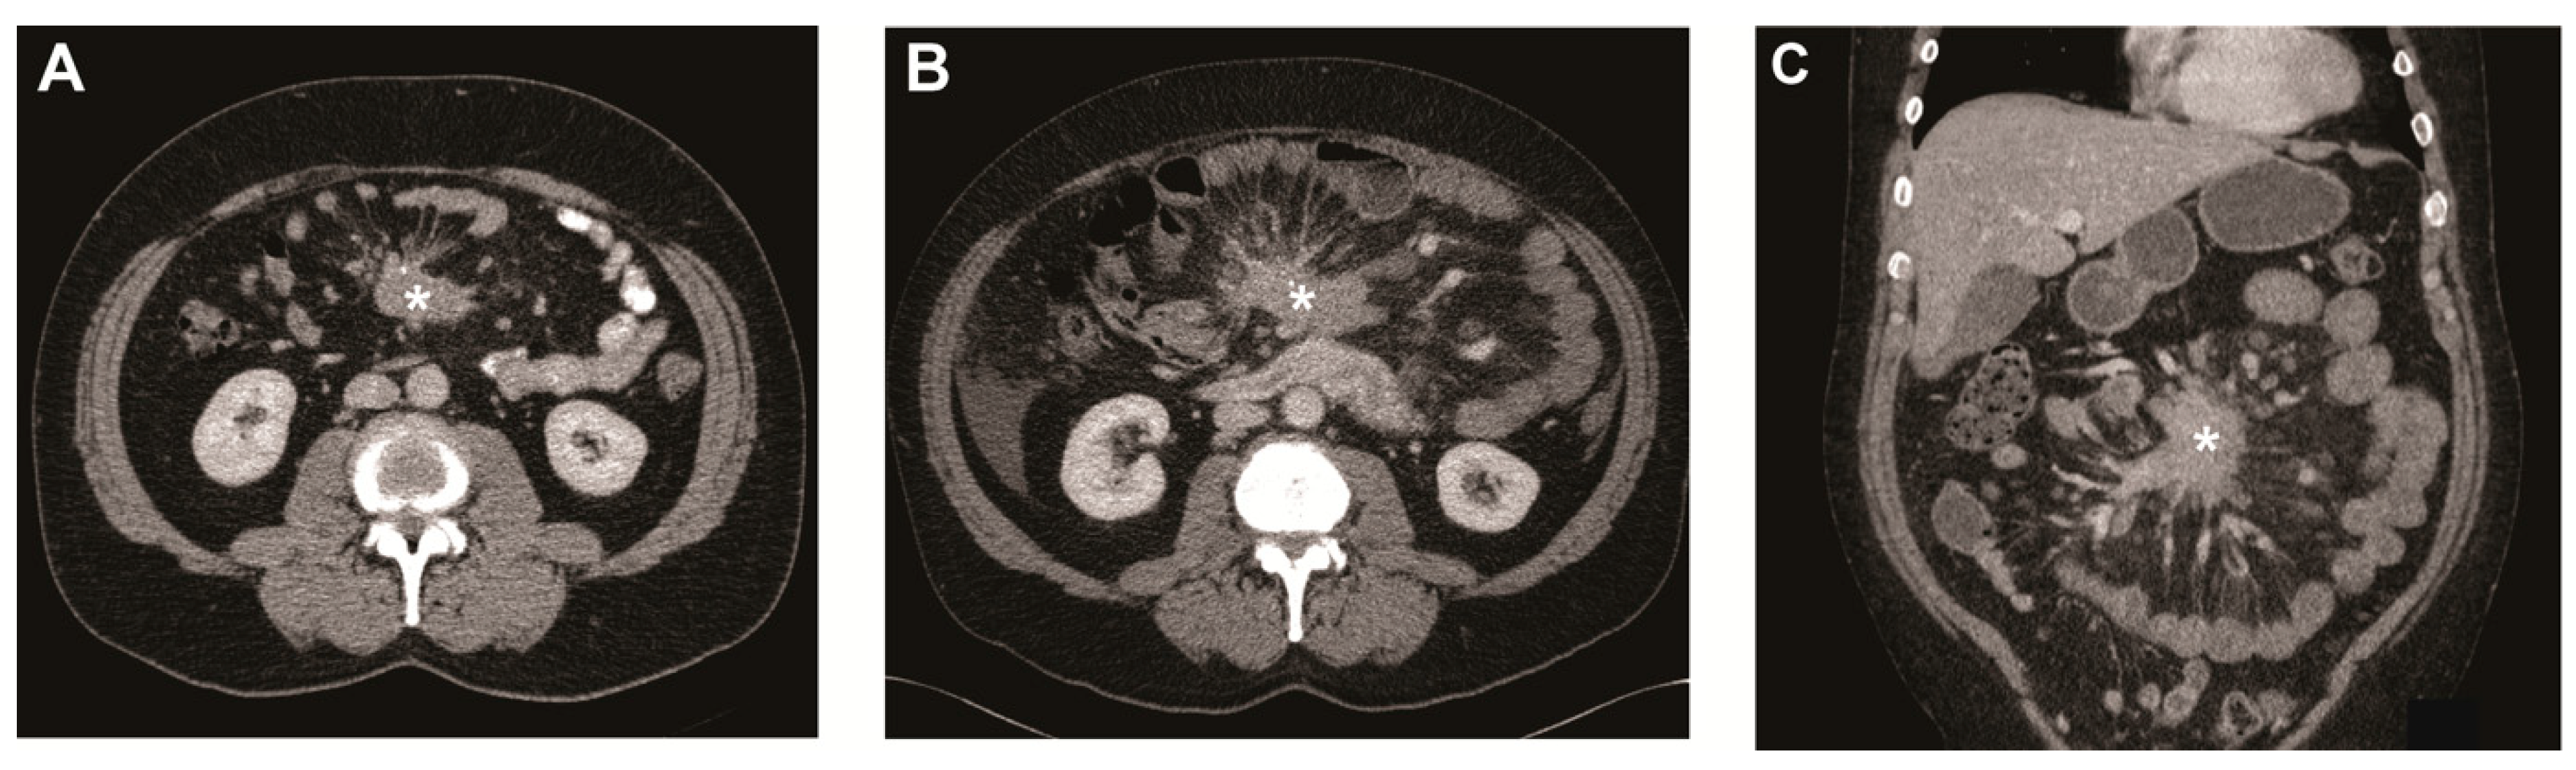

Figure 1.

Metastatic mesenteric mass and surrounding fibrosis over time. (A) Transverse image of CT scan at baseline showing mesenteric mass (asterisk) with radiating strands of fibrotic tissue. Transverse (B) and coronal image (C) of CT scan after 5 years showing the mesenteric mass (asterisk) growth of >20% on the short axis.

In the current study, we analyzed the evolution of mesenteric metastases in a large cohort of patients with SI-NETs with a median follow-up time of 34 months. In our cohort, a metastatic mesenteric mass was present in 64% of the SI-NET patients. During follow-up, growth of the mesenteric mass was noted in a minority (13.5%) and when present, the time to growth was remarkably long with a median of 40 months (see Figure 1). Moreover, the development of a mesenteric mass in patients without mesenteric disease at baseline was very rare and only observed in five patients (2.6%).